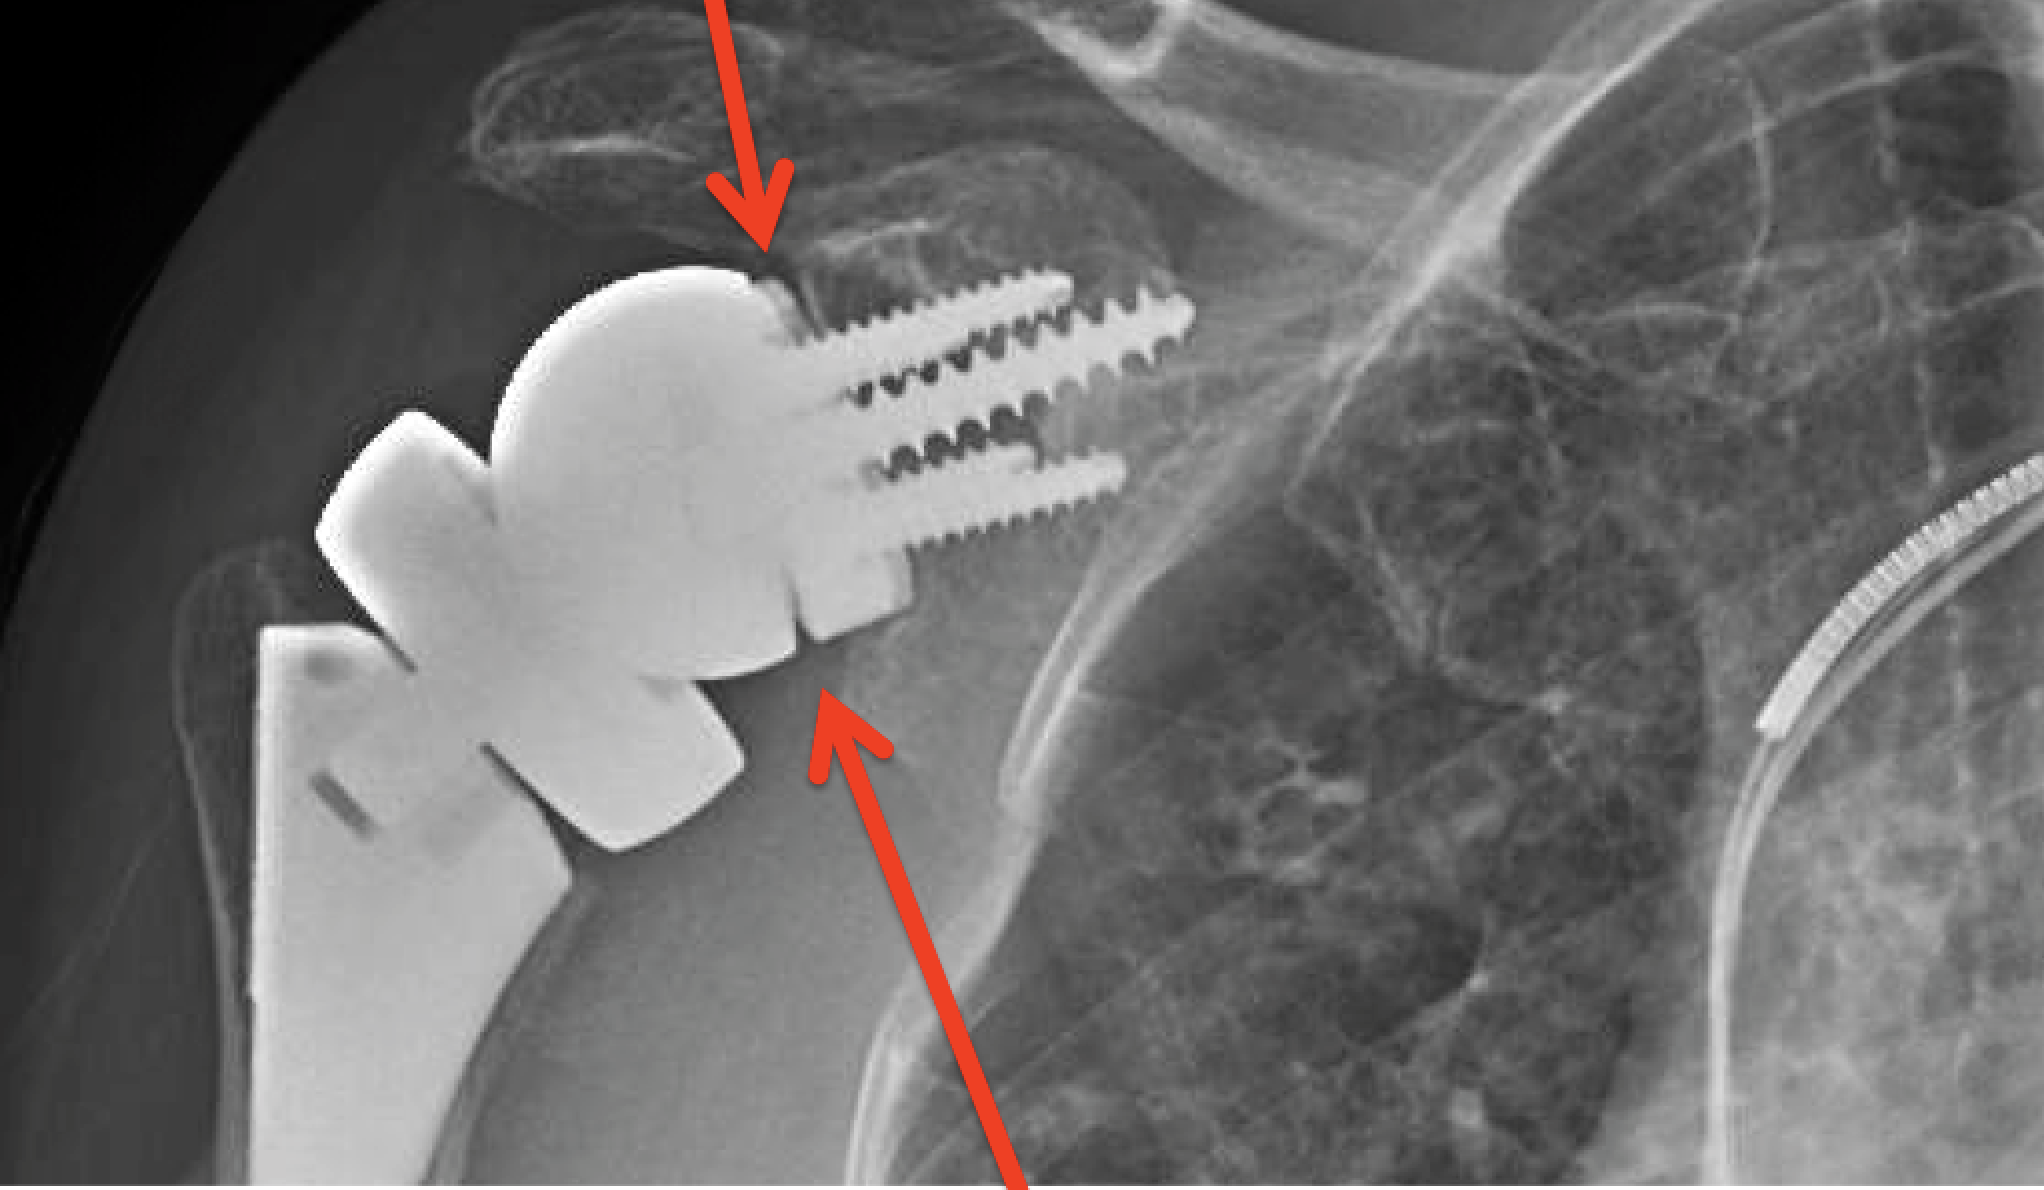

Shoulder Replacement X Rays . Reverse shoulder arthroplasty, total shoulder. the most common indications for shoulder arthroplasty are osteoarthritis, inflammatory arthritis, proximal humerus fractures, irreparable. shoulder arthroplasties are a common procedure, being third in joint replacements after knees and hips, and are used to treat a number of. shoulder replacement removes damaged areas of bone and replaces them with parts made of metal and plastic (implants). This article is chiefly limited to the routine radiographic evaluation of shoulder arthroplasties and guidelines to. shoulder arthroplasties are divided into three categories: They can show loss of the normal joint space between bones, flattening or irregularity in the shape of the bone, bone spurs, and loose pieces of cartilage or bone that may be floating inside the joint. shoulder arthroplasty is the primary treatment of advanced glenohumeral arthritis once conservative measures fail, can restore function to.

Shoulder Replacement X Rays shoulder arthroplasty is the primary treatment of advanced glenohumeral arthritis once conservative measures fail, can restore function to. shoulder arthroplasties are divided into three categories: shoulder arthroplasties are a common procedure, being third in joint replacements after knees and hips, and are used to treat a number of. the most common indications for shoulder arthroplasty are osteoarthritis, inflammatory arthritis, proximal humerus fractures, irreparable. shoulder replacement removes damaged areas of bone and replaces them with parts made of metal and plastic (implants). They can show loss of the normal joint space between bones, flattening or irregularity in the shape of the bone, bone spurs, and loose pieces of cartilage or bone that may be floating inside the joint. Reverse shoulder arthroplasty, total shoulder. shoulder arthroplasty is the primary treatment of advanced glenohumeral arthritis once conservative measures fail, can restore function to. This article is chiefly limited to the routine radiographic evaluation of shoulder arthroplasties and guidelines to.

Shoulder Arthritis / Joint Replacement True anteroposterior xrays Shoulder Replacement X Rays This article is chiefly limited to the routine radiographic evaluation of shoulder arthroplasties and guidelines to. Reverse shoulder arthroplasty, total shoulder. shoulder arthroplasties are divided into three categories: the most common indications for shoulder arthroplasty are osteoarthritis, inflammatory arthritis, proximal humerus fractures, irreparable. shoulder arthroplasties are a common procedure, being third in joint replacements after knees and. Shoulder Replacement X Rays.

Reverse Total Shoulder Replacement Dr Sunil Reddy Shoulder Replacement X Rays They can show loss of the normal joint space between bones, flattening or irregularity in the shape of the bone, bone spurs, and loose pieces of cartilage or bone that may be floating inside the joint. the most common indications for shoulder arthroplasty are osteoarthritis, inflammatory arthritis, proximal humerus fractures, irreparable. shoulder arthroplasties are a common procedure, being. Shoulder Replacement X Rays.